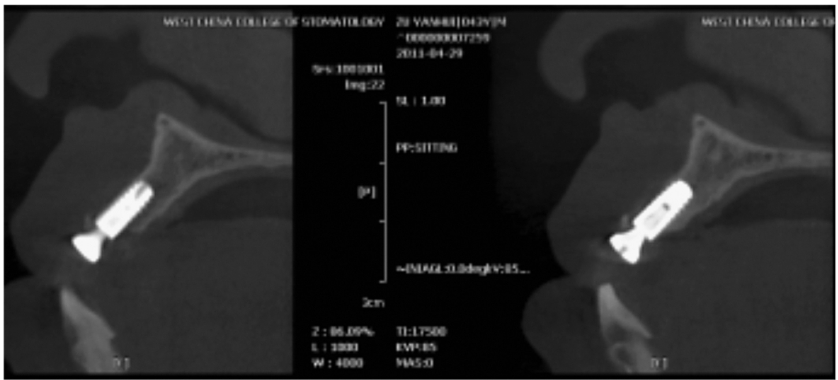

图7 术前矢状位

CBCT片显示牙槽骨密度低,正在愈合中

图8 术后CBCT片矢状位

显示种植体植入5个月后2期修复前的状况